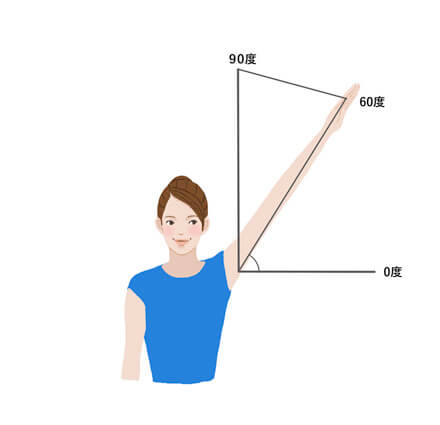

1. 壁に背をつけて、まっすぐ立つ

2. 手のひらを下に向けて肘を伸ばした状態で、壁に沿わせるように腕をゆっくり上げる

3. 肩の水平ラインを0度として、そこから腕があがったところまでの角度で、肩甲骨の状態を判定する

60度以上~90度…肩甲骨まわりの筋肉の柔軟性が保たれている

0度~60度未満…肩甲骨まわりの筋肉の動きが少し硬くなっている、肩甲骨まわりの筋肉の動きがガチガチに固まっている

このセルフチェックでは、腕を上げる時に必ず生じる肩甲骨の動きが適切にできているかを確認しています。そのため、腕を上げられる角度で肩甲骨まわりの筋肉の柔軟性が分かります。

セルフチェックを行ってみて、60~90度まで腕が上がった方は肩甲骨まわりの筋肉の柔軟性が保たれていますが、硬くならないように日常生活にストレッチを取り入れましょう。また、0~60度しか腕を上げられなかった方は、筋肉以外にも原因がある可能性があります。専門的な治療の必要性が考えられるため、整形外科など医療機関を受診しましょう。